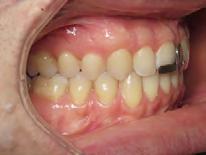

Approximately six months after insertion of the RPE, digital scans were taken for SureSmile custom wires and the patient was scheduled for the SFOT procedure with the oral surgeon. The RPE was removed, SureSmile wires inserted and segmental corticotomies performed, immediately followed by further vertical elastics on the right side (Figure

4). Archwires were upgraded incrementally into 19 x 25 SS. Once the bite was completely closed, the patient was referred to the myofunctional therapist to begin treatment. Eight sessions of myofunctional exercises were performed, focusing on muscle building, toning, synchronicity and awareness. Improvement in correct chewing, swallowing and resting postures of the lip and tongue were addressed. All appliances were removed 21 months after initial insertion (Figure 5), and the patient was referred to a re-

Figure 4. Post-corticotomy, with SureSmile custom wires.